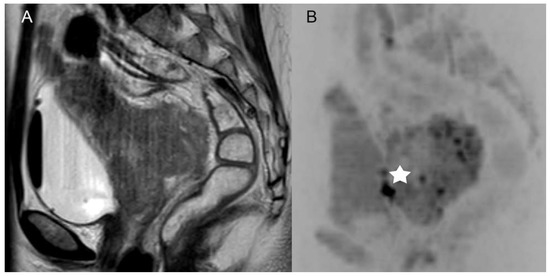

Figure 3. Example of a patient with a FIGO IV cervical carcinoma with a biopsy proven infiltration of the mucosa of the bladder which had not been recognized by both readers in the standard MRI ((A), sagittal T2-weighted scans without fat saturation), but was recognized in DWIBS (B), marked with a white star (*).